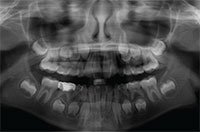

What Is This?

What is going on with the UL34?